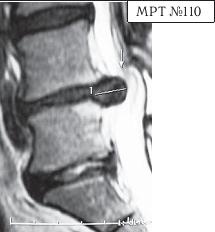

На МРТ № 108 состояние шейного отдела позвоночника пациента через 11 месяцев после дискэктомии с межтеловым спондилодезом в сегменте СIV—СV Наблюдается постхирургическая травма спинного мозга на данном уровне хирургической фрезой, кифозирование физиологического лордоза, стеноз позвоночного канала с блоком ликворных путей. На МРТ № 109 состояние шейного отдела позвоночника того же пациента через 23 месяца после дискэктомии с межтеловым спондилодезом в сегменте CIV-CV Наблюдается усугубление стеноза (абсолютный стеноз), спондилолистез (смещение вышележащего позвонка по отношению к нижележащему) СII— СIII, секвестрированная грыжа межпозвонкового диска CV—CVI. На данных снимках наглядно отображается, как подобные операции усугубляют биомеханические нарушения и тем самым способствуют развитию дегенеративно-дистрофического процесса в других сегментах позвоночника. Во время операции грыжу межпозвонкового диска в данном сегменте убрали. Но причины, которые как раз и спровоцировали образование грыжи, а именно биомеханические нарушения (дегенерация выше- и нижележащих межпозвонковых дисков, стеноз, кифоз), как были, так и остались! Несмотря на то что отдалённые последствия этой операции легко прогнозировались и полученный результат, как факт, абсолютно закономерен, подобные операции, к сожалению, как делались, так и делаются и, пожалуй, самое печальное, что и будут делаться дальше. Случаи послеоперационных рецидивов грыж межпозвонкового диска бывают разные, но причины, как правило, идентичны. Вот одна из типичных ситуаций. Врачи во главе с хирургом после хирургической операции пациента по поводу грыжи межпозвонкового диска в сегменте LV-SI в качестве профилактики посоветовали ему заниматься вытяжением позвоночника под собственным весом и укреплением мышечного корсета путём выполнения специальных упражнений на наклонной плоскости. Результат усердия пациента, последовавшего такому совету, можно наблюдать на МРТ № 110 (см. стр. 286). Исходя из анатомического и физиологического строения позвоночника человека и неизбежного действия законов физики, результат от такой «профилактики» вполне прогнозируем. Поэтому логично предположить, что врачи, посоветовавшие данному пациенту такую «профилактику», спровоцировавшую секвестрированную грыжу межпозвонкового диска в сегменте L^ — Ly, просто не знали о её последствиях. Если бы здоровье пациента позволило бы продолжить эти упражнения, то аналогичные осложнения неизбежно образовались бы и в вышележащих позвоночнодвигательных сегментах. ![]() На МРТ № 110 наблюдается состояние поясничного отдела позвоночника: секвестрированная грыжа межпозвонкового диска в сегменте LIV-LV с разрывом задней продольной связки, абсолютный стеноз спинномозгового канала. Но не спешите обвинять хирургов. Как бы это странно не звучало, это не их вина — они всего лишь удаляют часть ткани организма (грыжу). Ведь профессия хирурга заключается в знании и умении оказать пациенту своевременную хирургическую помощь, а вот послеоперационным восстановлением и «профилактикой» должны заниматься врачи-реабилитологи. Даже самые лучшие хирурги в мире, в совершенстве владеющие своей специальностью, за пределами операционной становятся обыкновенными людьми, которым, как и многим, свойственен относительный процесс познания. Требовать от них большего, это значит требовать от человека абсолютного процесса познания. Если вы считаете, что на это способен любой человек, попробуйте начать с себя. Гораздо хуже, когда врачи-реабилитологи в качестве «профилактики» дают такие «советы», вот это уже можно назвать профессиональной безграмотностью. Вот ещё случаи послеоперационных рецидивов грыж — естественной реакции организма, когда проблема решается однобоко — всего лишь с помощью хирургической операции в поражённом сегменте без общего восстановления биомеханики позвоночника.